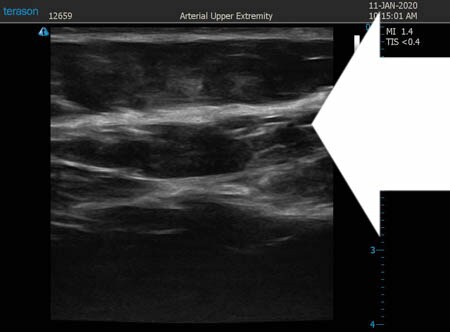

いつものように3Dタッチビュー(超音波)で

皮下脂肪層を評価してみましょう。

上腹部

↓ ↓ ↓